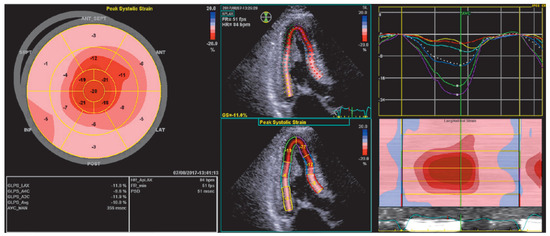

The Eustachian ridge is ablated as part of the cavotricuspid isthmus (CTI) involved in typical atrial flutter (AFL) ablation, but is itself rarely an arrhythmogenic focus. We report a case of a patient with dual tachycardia involving the CTI area....